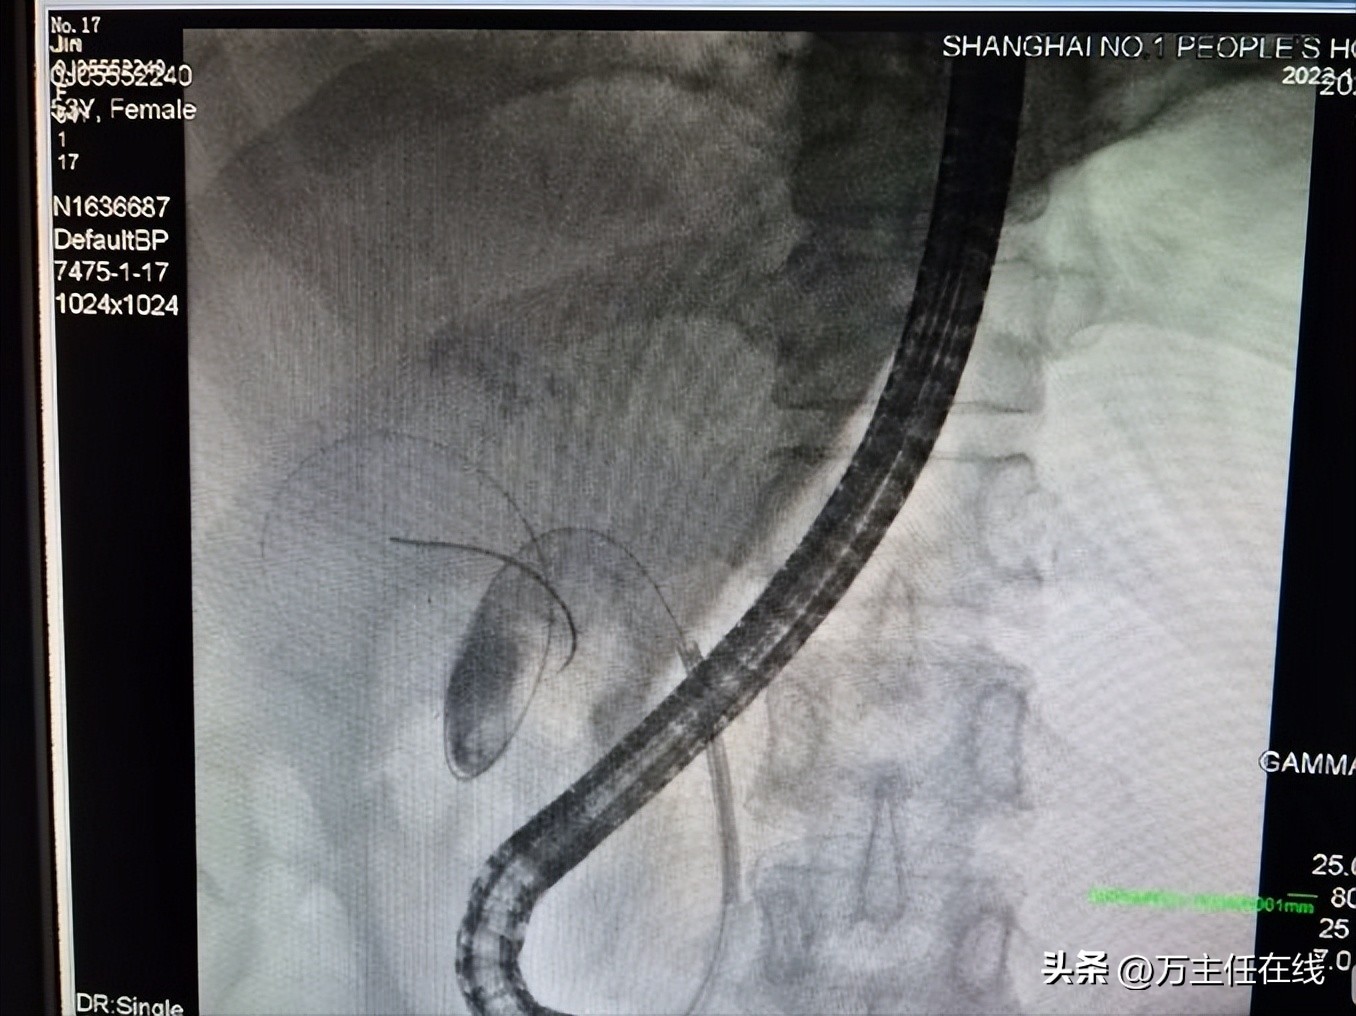

Spyglass下导丝将胆囊颈部结石拨离解除嵌顿,并胆囊内球囊清理并反复冲洗胆泥

胆囊管置入后